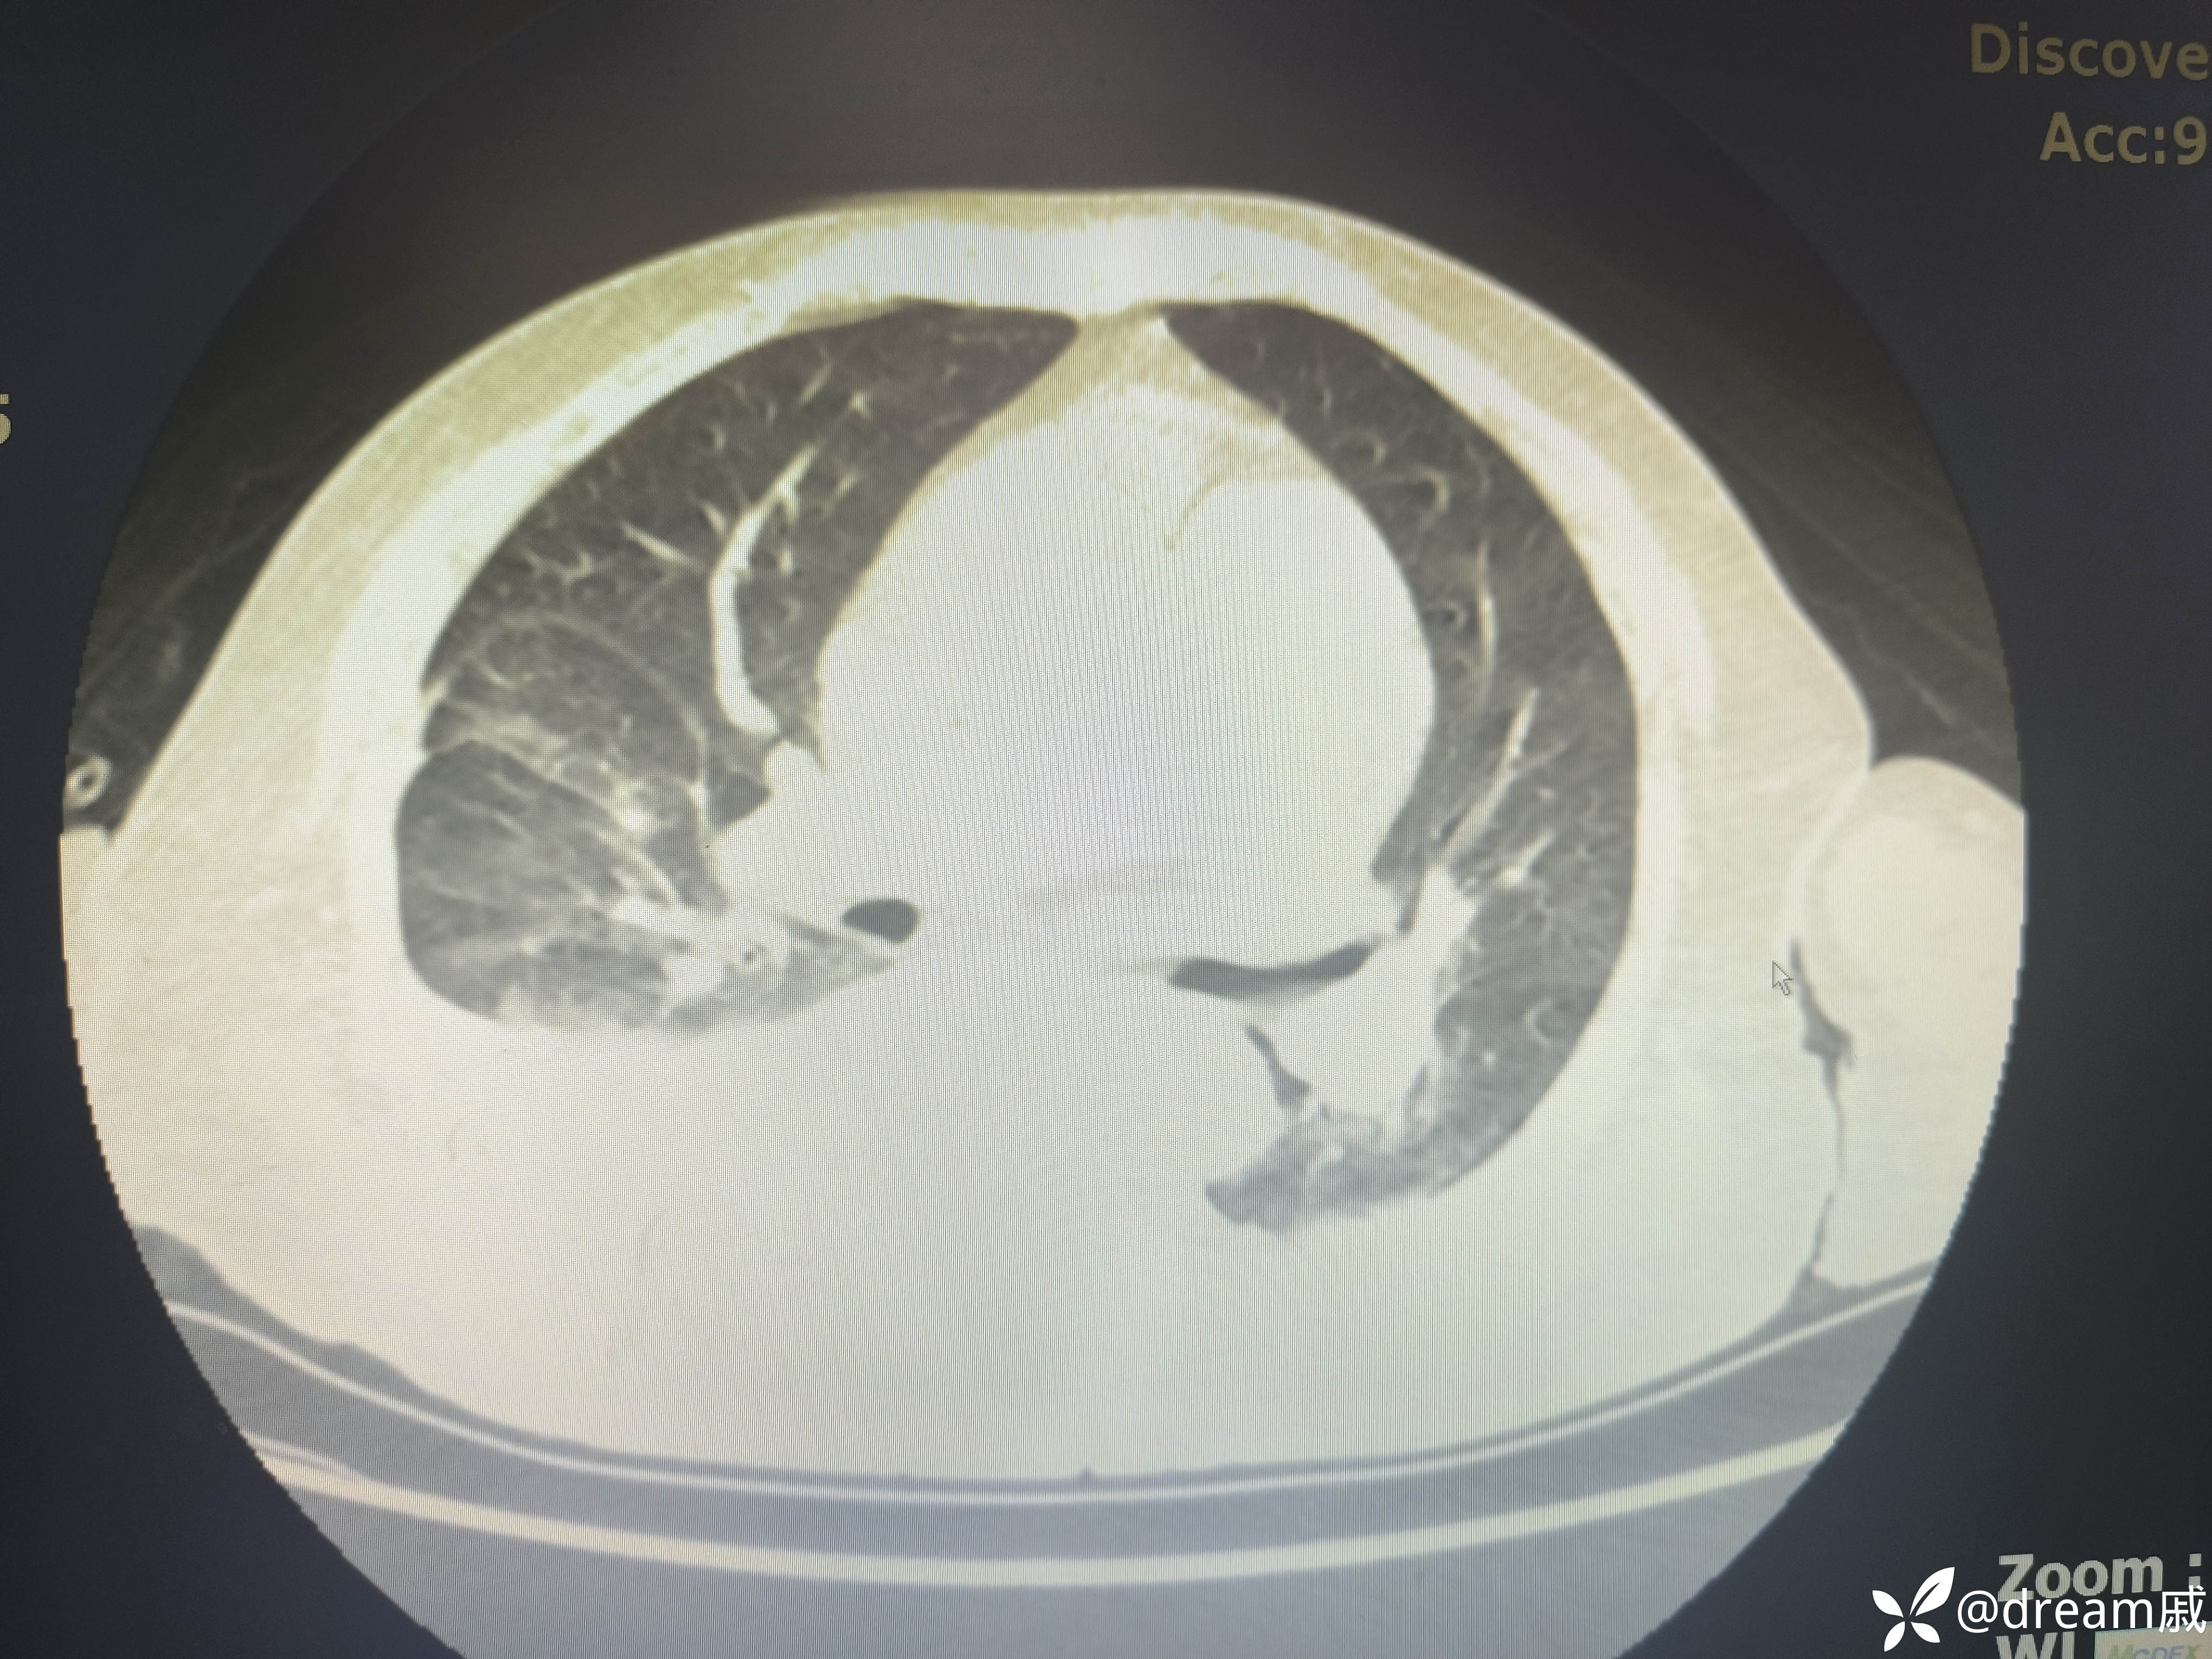

胸部CT示右肺中下叶斑片影,双肺局部间质性改变。

5月27日复查CT如下